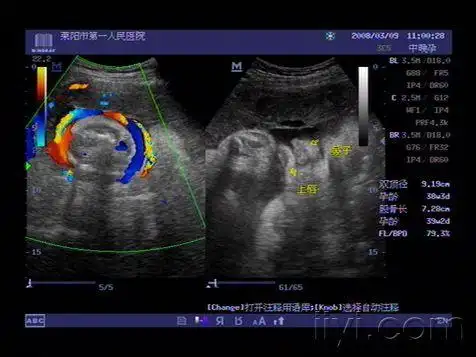

超声在胎儿颈部观察有无脐带回声,彩色血流观察脐带血流情况.